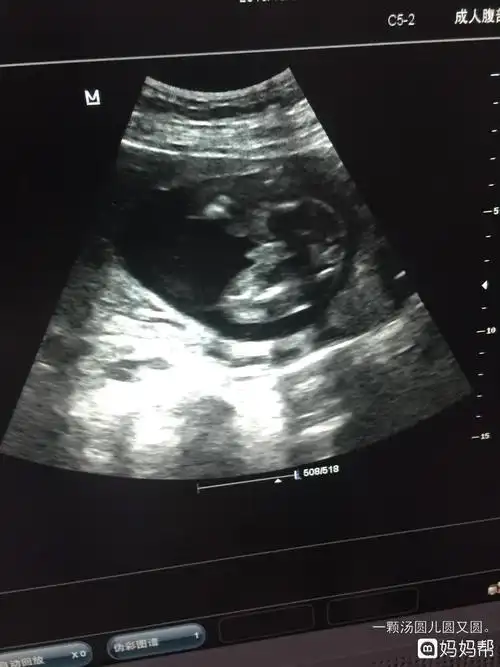

男女胎儿b超发育全过程高清图

怀孕3个月男女胎儿差异大:4件小事孕妇要常放在心上,尤其第1件

【怀孕几个月可以看男女】怀孕几个月可以看出胎儿性别_几周可以看出